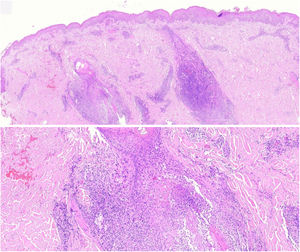

Los cortes histopatológicos en los que se dio el diagnóstico de MFF fueron evaluados por 2dermatopatólogos (SM y XR) cegados para los datos clínicos y de seguimiento. Los parámetros histológicos evaluados fueron basados en los estudios de Santen et al.12,16,17 y son los siguientes: subtipo histológico (1. enfermedad temprana o parche; 2. placa temprana; 3. placa avanzada; 4. tumor); extensión del infiltrado neoplásico (1. escaso; 2. prominente perifolicular y perivascular confinado al área perifolicular; 3. confluente perifolicular e interfolicular; 4. completo difuso); porcentaje de células atípicas en el infiltrado (< 10%; 11%-25%; > 25%); grado de foliculotropismo (leve, moderado y extensor); epidermotropismo (ausente o presente); siringotropismo (ausente o presente); mucinosis folicular (ausente o presente); infiltrado eosinófilo (ausente o presente); expresión de Ki-67 (menor del 10% o mayor al 10%), además de incluir la presencia de otros hallazgos microscópicos como la transformación a célula grande o el fenotipo CD8. Las placas fueron evaluadas en hematoxilina eosina y con marcadores de inmunohistoquímica (se presenta un ejemplo de placa temprana [fig. 1] y de avanzada [fig. 2]).

Placa temprana. Se observa un infiltrado linfoide atípico escaso perifolicular, con mucinosis folicular prominente, epidermotropismo con disposición lineal de los linfocitos en banda en la unión dermoepidérmica, llamando la atención el fondo fibrótico y con poiquiloderma, además de algunos queratinocitos apoptóticos y melanófagos.